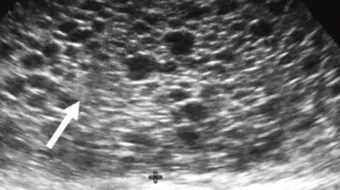

هو أحد أنواع الحمل التي عادةً تستمر، ويُمكن أن تُؤدّي الى مُضاعفات للسيدة، وهو عبارة عن إخصاب حَيوانين منويين في بُويضة فارغة فيما يتسبّب في حدوث مُشكلة في عدد الكروموسومات. عند فَحص السيّدة المُصابة بالحمل العنقودي تكون نتيجة فحص الحمل إيجابيّةً، لكن لا يظهر الجنين على جهاز الالتراساوند.